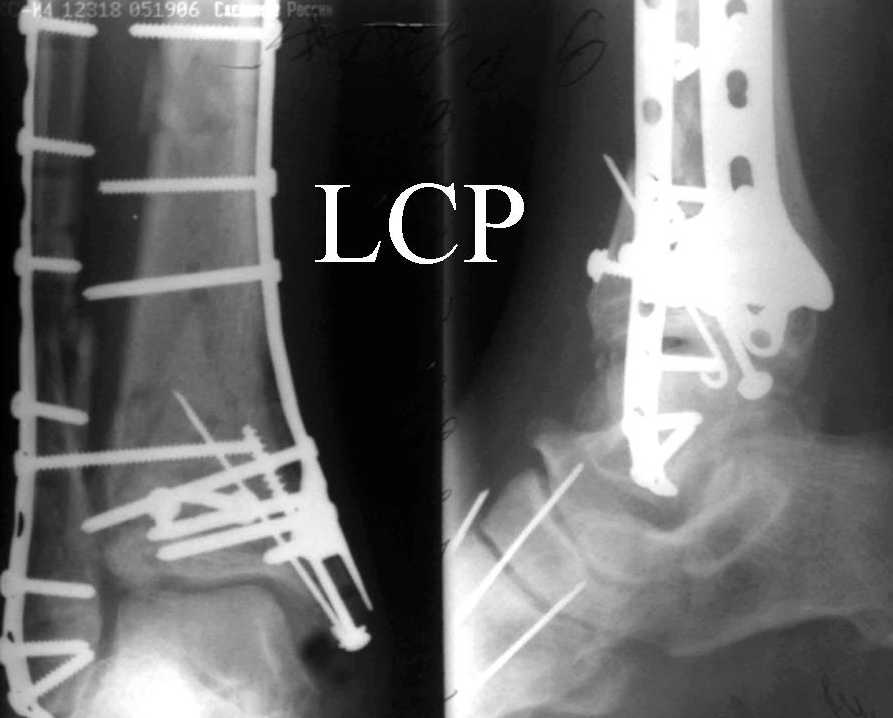

На рентгенограммах типичный перелом пилона по типу С-3. есть опыт до 100 открытых опреаций у нас в клинике. 20 примерно в год. Принцип один -все внутрисуставные переломы нуждаются в открытой репозиции и внутренней стабильной фиксации. При поступлении КТ не надо, так как получается только нагромождение костей. Истинной картины нет. Главное восстановить длину малоберцовой кости - это ключ к успеху. При поступлении меньше всего надо думать о сосудистых расстройствах, т.к. сама операция и репозиция даже сначала частичная даёт улучшение сосудитых нарушений. Причём очень быстро. Операция в 2этапа. При поступлении доступ позади наружной лодыжки, причём обязательно. После этого репозиция малоберцовой кости и фиксация пластиной 1/3 трубки под винт 3,5. Дренаж и любой аппарат наружной фиксации. Затем после спадения отёка на 5-7-10 день аппрат снимается и дугообразный разрез спереди от медиальной лодыжки 10-12 см. Главной чтобы расстояние между 1 и вторым разрезом было не меньше 7-8 см. Тогда не будет некрозов лоскутов. Таранная кость используется как матрица на неё укладываются отломки и фиксируются пицами. Ренг-контроль. Отломки лежат все отдельно, но ничего не высыпется. При переломах С-3 всегда нужна костная пластика (из крыла). Фиксация пластиной лист клевера простой или LCP. Гипс не нужен. Дренаж до 48 часов. Операция длится 3-4 часа обязательно без жгута. Посылаю примерно такой же случай.

Послала ещё два снимка, если не пройдут, пошлю ещё. Дрягин. Если есть вопросы, готов ответить.